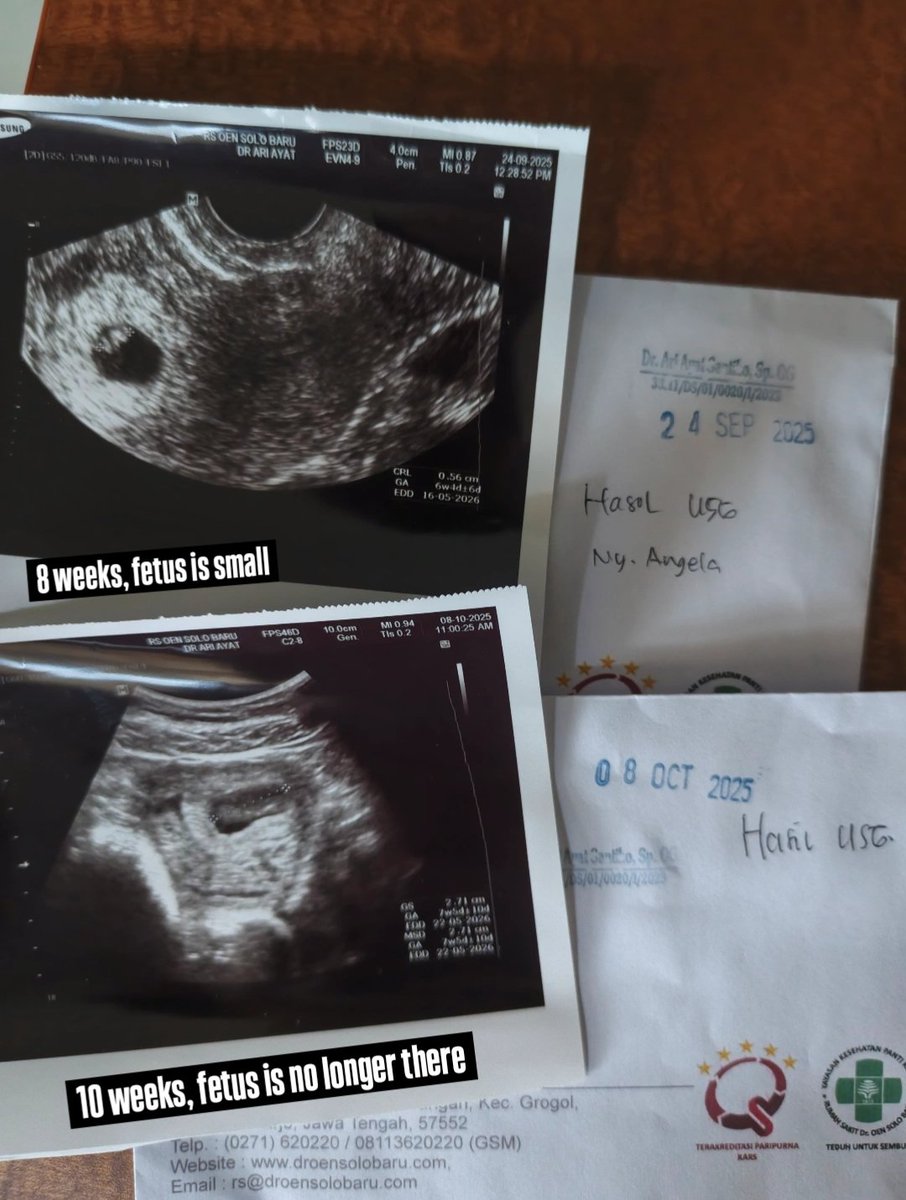

Sadly after 2 months, things didn't go as well as we had hoped and had a miscarriage, so I'm going to go through curettage. Sorry everyone but once again I would need to delay work for a couple more days, I'll try my best to get back ASAP. Thank you so much for your patience 🙏

After getting my surgery back in July, I am finally able to conceive! I went through laparoscopy drilling because of PCOS, good thing the recovery period is not as long as other surgeries. And then I found out a couple weeks ago that I'm pregnant, I am officially 7 weeks

I finally got pregnant after trying for 2 years! 🥺💜